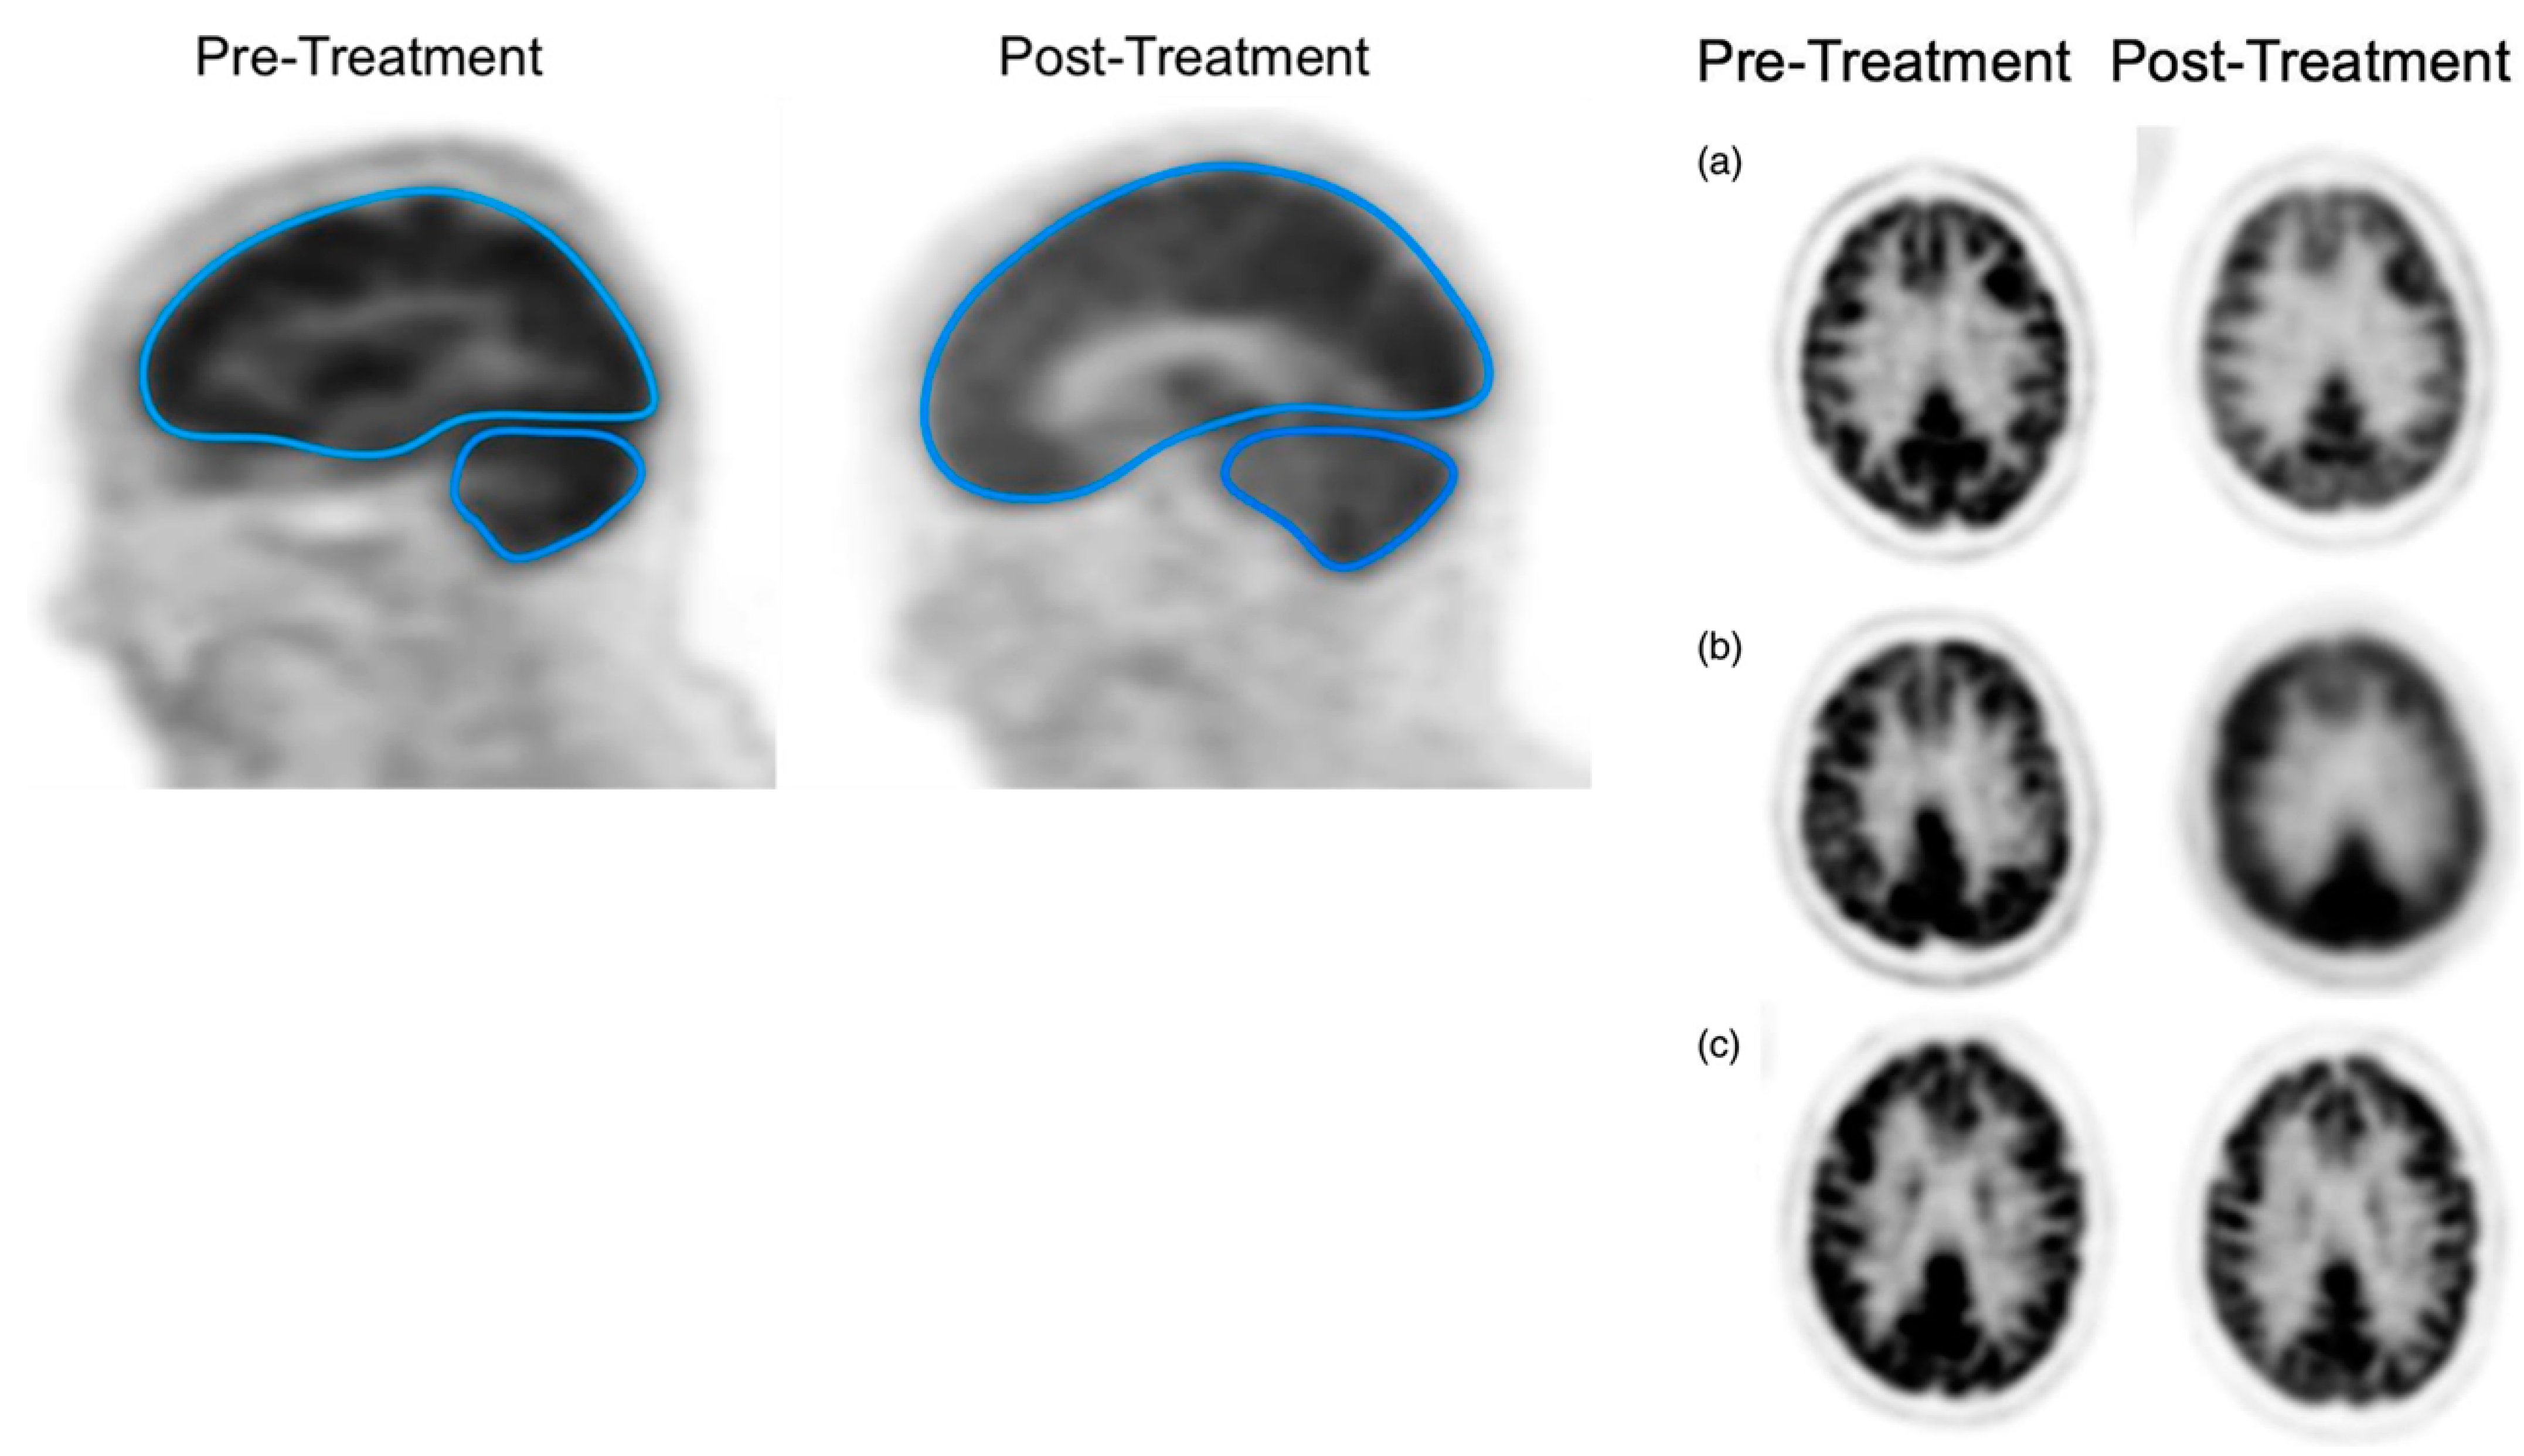

The existing literature indicates that a vast majority of commonly employed chemotherapeutic medications have the potential to induce adverse neurological reactions [43]. Cancer-related cognitive impairment (CRCI), encompassing problems such as cognitive decline, memory challenges, and difficulties with concentration, is a common complication observed in individuals undergoing systemic chemotherapy [44,45]. Research investigations have linked high-dose chemotherapy (HDC) to alterations in brain structure, such as decreased regional brain volume, degeneration of gray matter, and demyelination of white matter [46]. Examining CRCI, also known as chemo brain, has until recently been limited to research using clinical neuropsychological methods designed to detect localized brain lesions [46]. However, [18F]FDG is capable of detecting alterations in brain activity post-treatment, as it visualizes and quantifies changes in glucose metabolism [46].

In a recent study, the aim was to compare the effects of treatment—specifically, conventional standard-dose chemotherapy (CDC) versus HDC followed by autologous stem cell transplantation (HDC/ASCT)—on the overall brain glucose metabolism of MM patients [46]. The researchers employed a comprehensive brain [18F]FDG PET measurement approach for this purpose, providing an evaluation of changes in 18FDG metabolism throughout the whole brain (Figure 9) [46]. After treatment, a notable reduction in the GSUVmean (global standardized uptake value mean) was observed in the supratentorial brain and cerebellum of patients who underwent HDC/ASCT (p-values < 0.05) (Figure 9) [46]. Conversely, there were no statistically significant GSUVmean changes after treatment in patients who received CDC (Figure 9). The scientists concluded that a significant decrease in [18F]FDG uptake in the brain after treatment was only observed in patients who received HDC/ASCT [46]. This observation might suggest a tendency for chemo brain to be more prevalent in cases involving HDT [46].

Figure 9.

The left figures depict the use of designated regions of interest (ROIs) for the supratentorial and cerebellum areas within the brain of a multiple myeloma patient. The separation of the supratentorial region from the cerebellum was achieved using the tentorium cerebelli as a reference point. Patients (a,b) received high-dose therapy, whereas patient (c) received conventional chemotherapy, resulting in fewer changes in brain [18F]FDG uptake compared to patients (a,b).